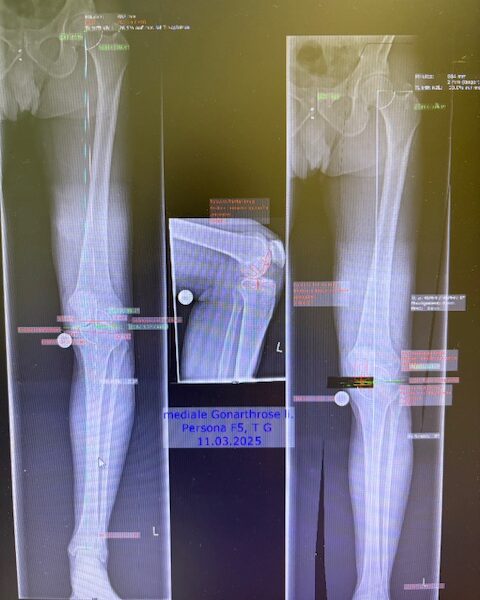

Ο προεγχειρητικός ψηφιακός σχεδιασμός

Πραγματοποιήθηκε απεικόνιση και ψηφιακός σχεδιασμός της επέμβασης, ώστε να προσδιοριστεί με ακρίβεια το μέγεθος και η θέση των προθέσεων. Ο στόχος ήταν να αποκατασταθεί η φυσιολογική μηχανική του γόνατος, διατηρώντας ανέπαφα τα υγιή τμήματα της άρθρωσης, τους συνδέσμους και τους γύρω μυς.